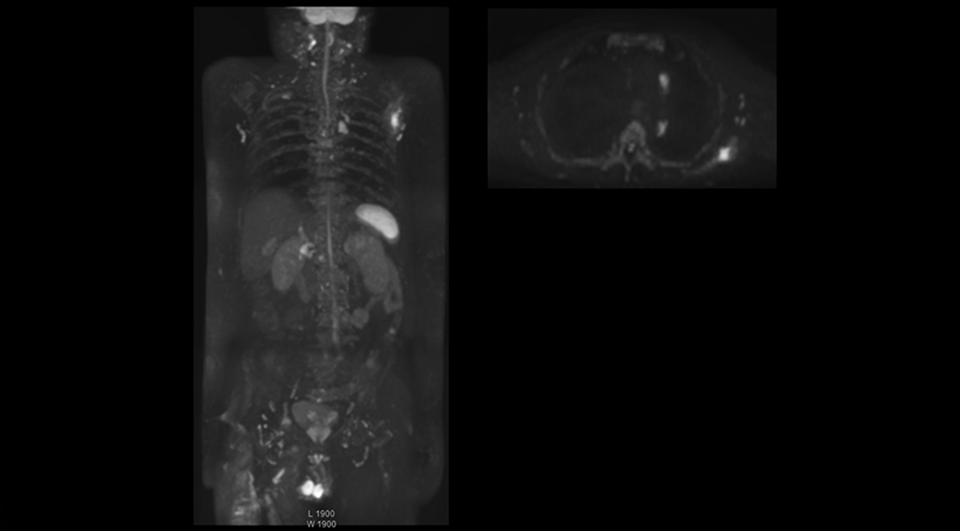

Recognizing the clinical utility of whole body MR imaging, radiologists at Kawasaki Saiwai Hospital (Kasawaki, Japan) began offering whole body diffusion weighted imaging (DWI) in 2009 for oncology patients. In 2012, the hospital installed a Philips scanner, the Ingenia 1.5T. The dStream digital architecture and highly linear gradients of Ingenia allowed them to switch to coronal – rather than axial – whole body DWI, and were key to developing a fast, high quality protocol that has led to increased referrals and decreased dependence on nuclear medicine imaging.

Coronal DWIBS is faster and improves image quality

“Switching to coronal DWIBS – rather than axial – further shortens scan time,” says Mr. Naka. “Important is that a dS SENSE factor of 5 shortens exam time while high image quality can be maintained, thanks to Ingenia’s dStream architecture.” He adds that the coronal orientation also avoids artifacts that are specific to combining axial images.

“When we use a coronal DWIBS acquisition, we can perform a full whole body examination, including other required sequences, within 30 minutes,” he says.

“This is considerably faster than the previously used exam with axial whole body DWI, which took more than 45 minutes,” he notes. “A shorter exam is more patient-friendly and allows us to also use it on patients in poor health who would have difficulty tolerating a long exam. Limiting the exam time is also helpful for scheduling, because it fits in a normal single exam timeslot.”